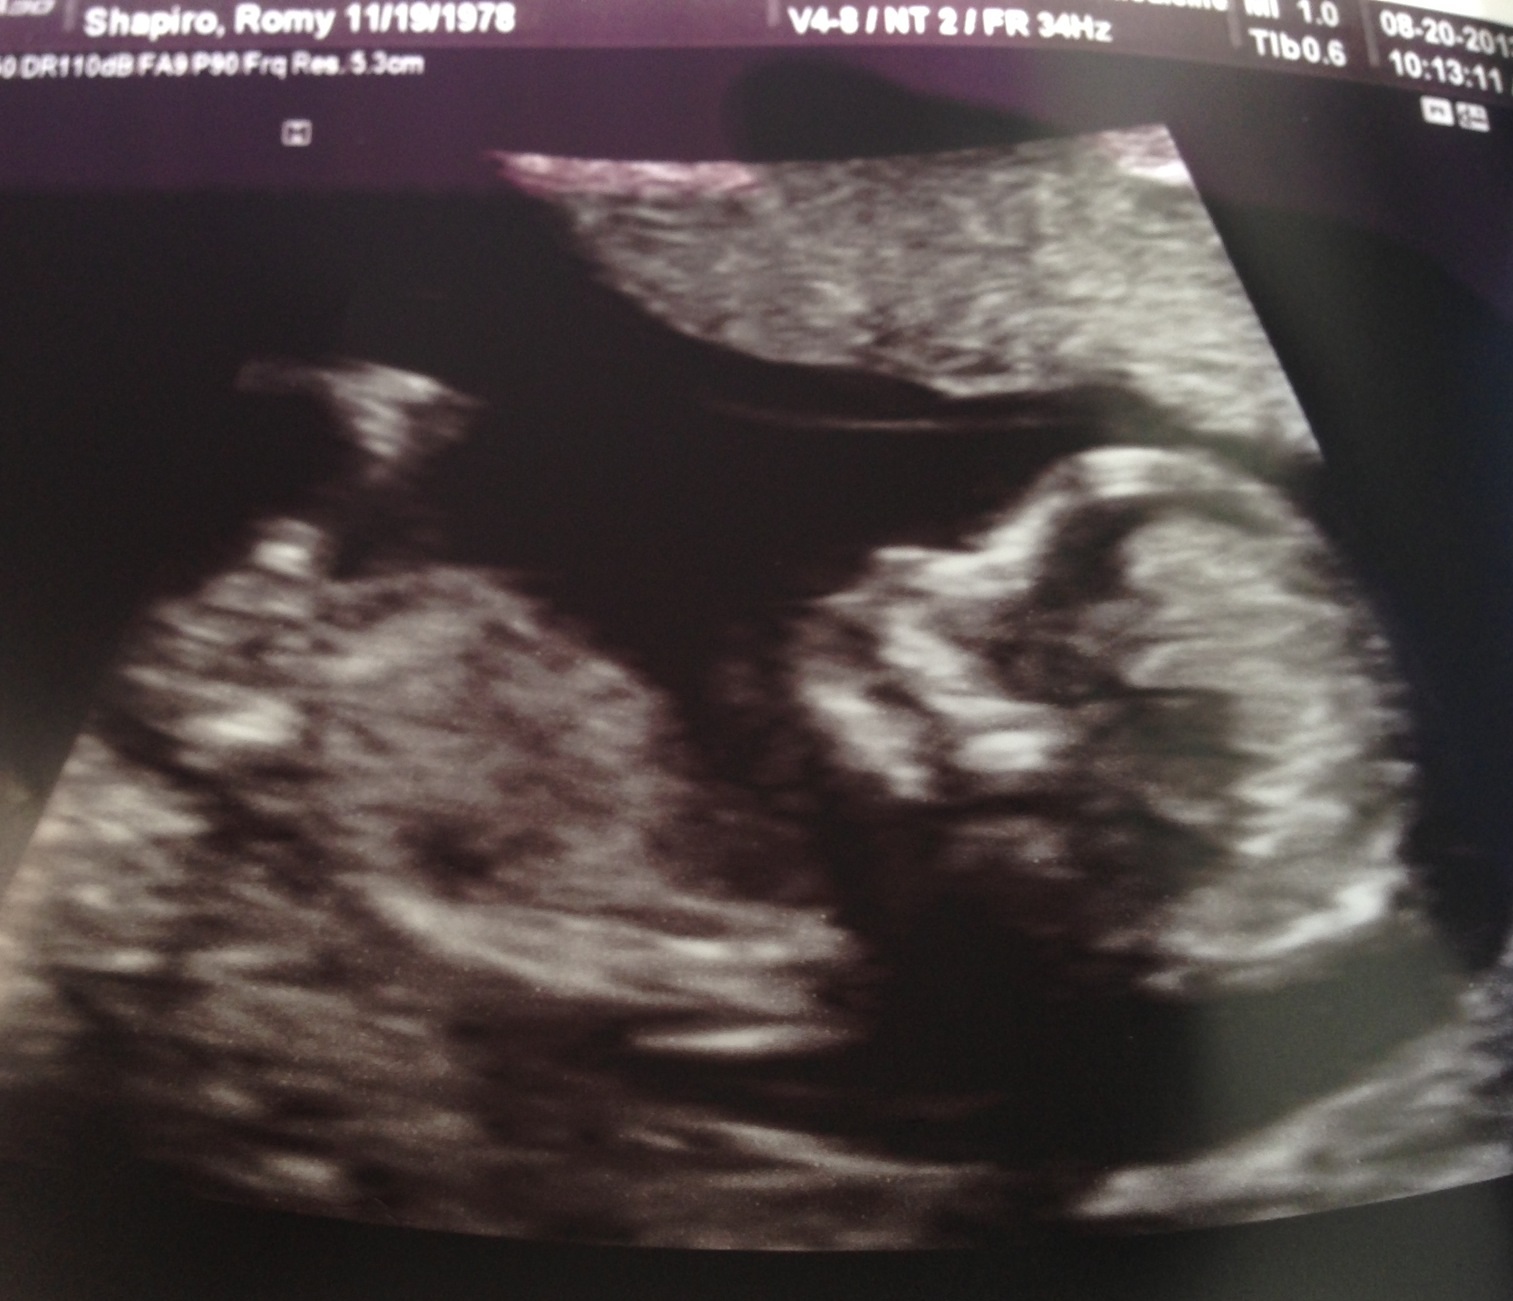

help!!! Tech says this is cord or leg and not nub. Is she telling the truth?!?!